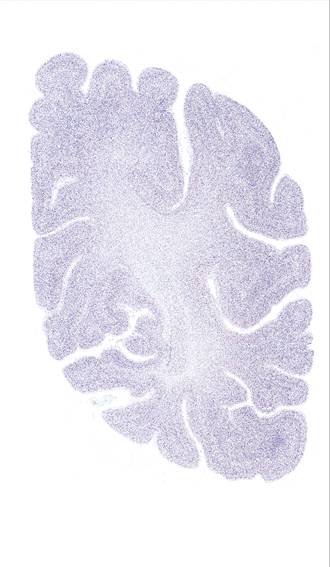

Hi-Resolution Sections · Cells (Nissl Staining) · Virtual Microscopy

Frontal sections (Nissl) from the Atlas Brain:

Slice ID:

r4-0720

Plate NR:

57

Position:

56,2 mm